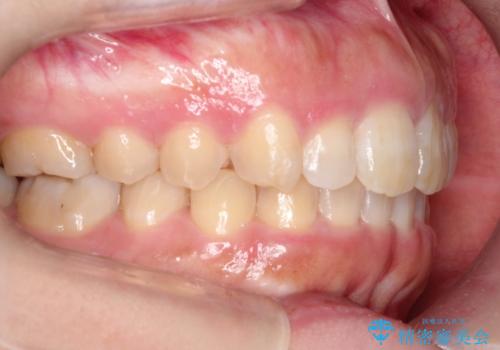

【出っ歯が気になる】インビザライン症例

- 前歯の歯並びの改善を希望され来院された患者様です。

初診時の歯並びの状態としては、上の前歯が下に対して前に飛び出た上顎前突という状態で、前歯は大きく前に飛び出した状態により患者様も口の閉じづらさを感じているとのことでした。また上顎に軽度の叢生(ガタガタ)がありました。

抜歯は行わず上顎の奥のスペースを利用して歯をスライドする方法の他に歯列弓の拡大やディスキング(歯と歯の間の隙間を作る処置)を行い叢生を改善しました。

奥歯を後ろに送る工程では上下でゴムかけをしていただきました。

矯正装置としてはマウスピースを使用しています。

見た目、嚙み合わせ及び、治療期間や施術内容に大変ご満足いただきました。